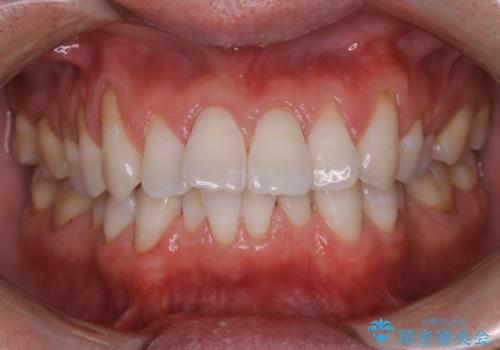

ホワイトニング 1日で真っ白な歯に

- ホワイトニングで歯を白くしたいとのことでした。

処置前クリーニング¥3300・オフィスホワイトニングのエクセレントコース¥29700を行いました。

- ¥33000費用は治療当時の料金となります